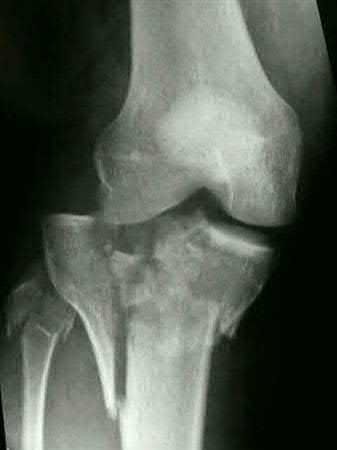

Question 18:

A 45-year-old male sustains a severe high-energy knee injury. Radiographs show a depressed, split fracture of the medial tibial plateau with extension into the intercondylar eminence (Schatzker Type IV). Which surgical approach is generally most critical to anatomically reduce and buttress the primary fracture fragment?

Options:

- Anterolateral approach

- Posteromedial approach

- Direct anterior parapatellar approach

- Posterolateral approach

- Direct medial approach

Correct Answer: Posteromedial approach

Explanation:

Schatzker IV fractures involve the medial tibial plateau. The primary fracture fragment in medial plateau injuries typically displaces posteromedially due to the pull of the semimembranosus and the medial femoral condyle's biomechanics. A posteromedial surgical approach is required to properly visualize, reduce, and place an anti-glide buttress plate on the posteromedial apex of the fragment. An anterolateral approach is utilized for Schatzker I, II, and III (lateral plateau) fractures.